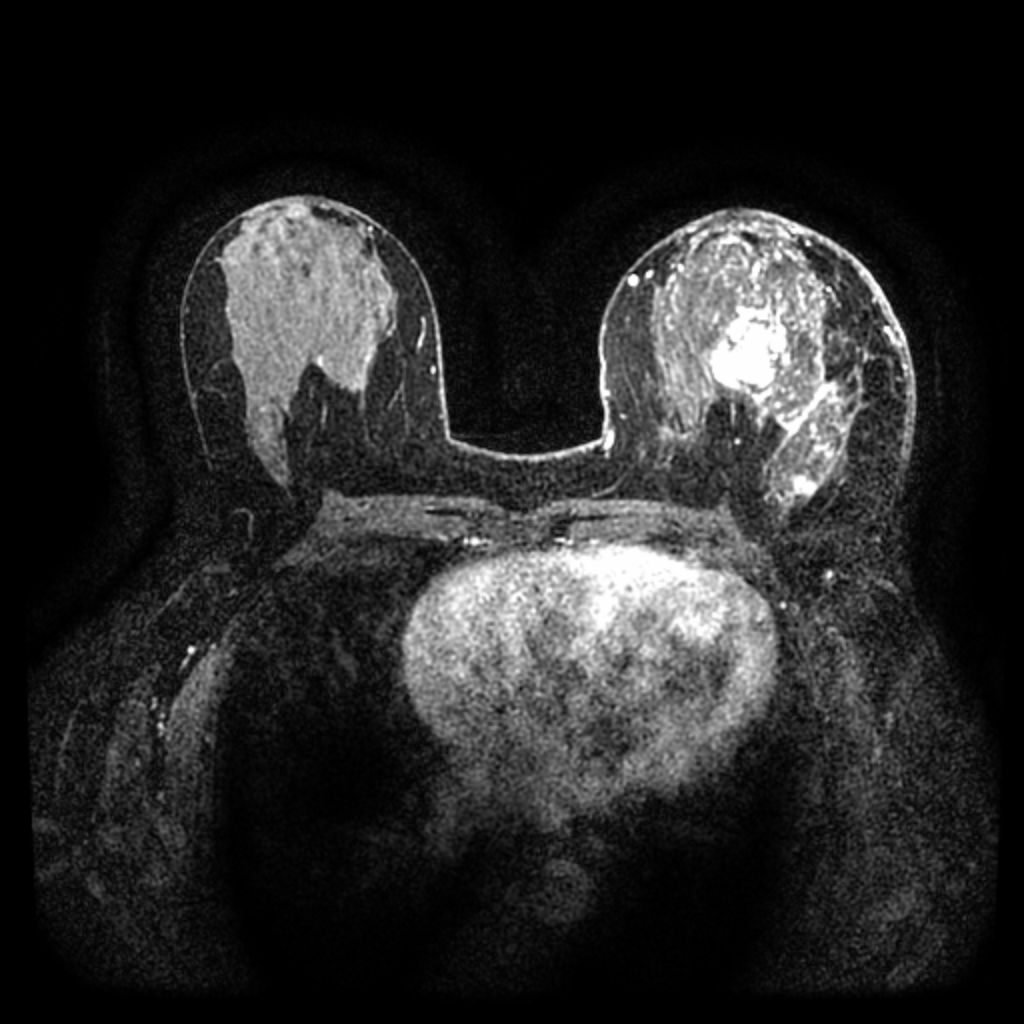

The task of the challenge is to synthesize 2D post-contrast breast DCE-MRI from corresponding pre-contrast DCE-MRI input. Participating algorithms operate on pre-contrast images where the malignant tumor is the largest and generate corresponding synthetic peak-enhanced post-contrast output.

Pre-contrast MRI

Post-contrast MRI

Peak-enhancement